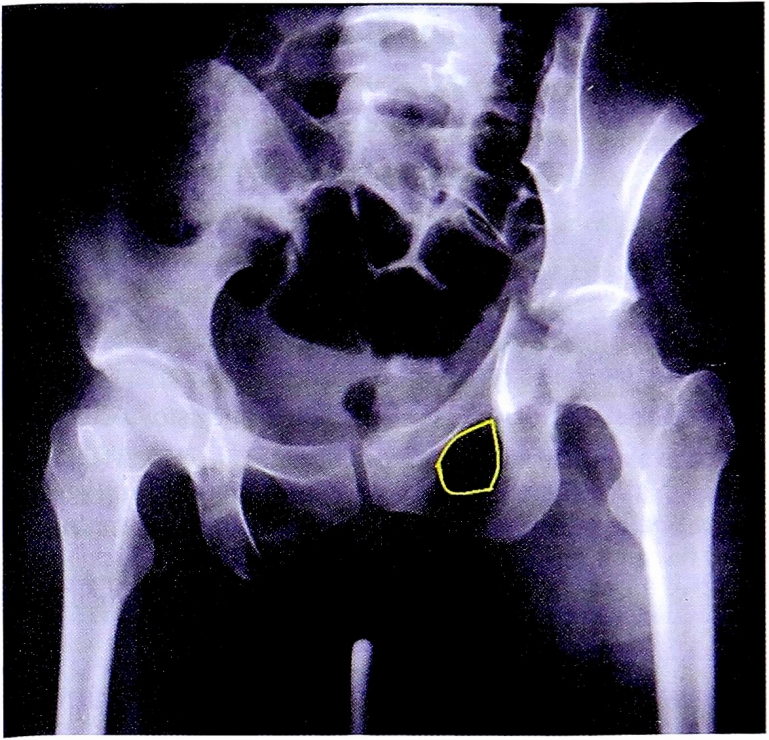

- Фигура слезы представляет собой передненижнюю часть суставной поверхности вертлужной впадины, имеющей подковообразную форму, соответвует медиальному отделу нижнего края суставной поверхности впадины. Является ориентиром для определения истинного положения дна вертлужной впадины (рис. 4).

Рис. 4. «Фигура слезы» на рентгенограмме и на схематическом изображении таза.

Fig. 4. Teardrop line on AP pelvic X-ray and on schematic pelvis.